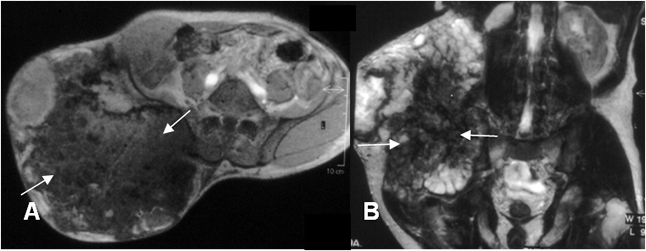

Fig 91. Condrosarcoma.

A: Rx AP y B: TAC axial. Gran masa de tejidos blandos de crecimiento agresivo, con calcificaciones en palomitas de maíz, secundario a condrosarcoma.

Fig 92. Condrosarcoma.

A: TAC axial en ventana de tejido y B: TAC axial en ventana osea. Lesión de comportamiento agresivo en el 2º dedo, con adelgazamiento de la cortical, masa de tejidos blandos y calcificación condroide de la matriz, por condrosarcoma.